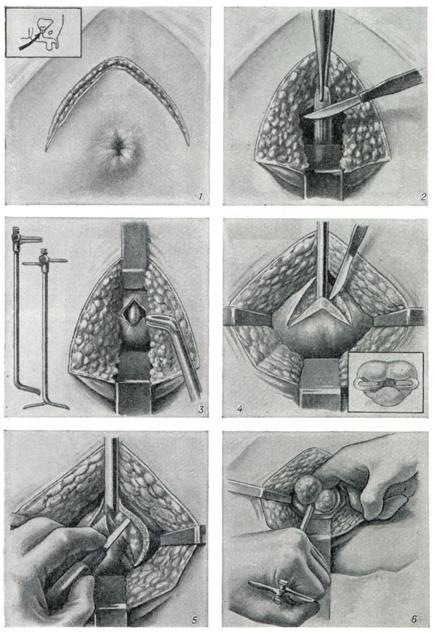

Одномоментная чреспузырная аденомэктомии по Федорову — Фрейеру (рис. 10). Эта операция отличается простотой подхода; летальность при ней около 2,0% . Она дополнена рядом приемов, направленных на обеспечение гемостаза путем наложения швов на края простатического ложа или ушивания его. Гемостаз при этой операции обеспечивается также применением катетера с баллоном типа Померанцева — Фолея (рис. 11). Уменьшение крово-потери ведет к уменьшению таких послеоперационных осложнений, как сепсис или почечная недостаточность.

3. Операция по методу Харриса — Гринчака (рис. 12) заключается вушивании простатического ложа после аденомэктомии под контролем глаза вокруг предварительно введенного катетера: удалив ткани, оставшиеся после энуклеации, на края простатического ложа накладывают швы бумеранговой иглой или обычной значительно изогнутой иглой на длинном иглодержателе. Если кровотечение полностью остановлено, пузырь может быть ушит наглухо; внижний угол раны на 2 суток вводят небольшой резиновый или марлевый выпускник. Постоянный катетер обеспечивает эвакуацию мочи в течение 10 дней. Этот метод дает хорошие результаты при тщательном послеоперационном уходе, особенно впервые 2 суток после операции:каждые 2 часа пузырь промывают теплым изотоническим раствором хлорида натрия или 3,8% раствором лимоннокислого натрия для предотвращения образования кровяныхсгустков.

4. Позадилобковая аденомэктомия(рис. 13) впервые предложена А. Т.Лидским и разработана Миллином(Т. Millin). Операция эта длительноевремя конкурировала с операциейХарриса.

В настоящее, время ее применяют реже из-за наблюдавшихся осложнений — до 15% . Больного укладывают в положение Тренделенбурга с разведенными ногами; подход к предстательной железе осуществляется через вертикальный или поперечный надлобковый разрез. Брюшинную переходную складку отводят вверх; позадилобковую клетчатку осторожно отводят вниз и латерально, избегая обнажения задней поверхности лобкового сочленения. Большие вены, лежащие в фасции на передней стороне предстательной железы, рассекаются между лигатурами. Собственную капсулу предстательной железы вскрывают поперечным разрезом на 1 см ниже шейки мочевого пузыря.

Аденому предстательной железы удаляют из капсулы частично длинными кривыми ножницами, частично пальцем, выделяя ее вплоть до стенки мочевого пузыря; пересечением центральной части мочеиспускательного канала у самой шейки мочевого пузыря удаляют опухоль.

Для предупреждения обструкции после аденомэктомии иссекают манжетку слизистой оболочки из задней дуги шейки мочевого пузыря. Гемостаз обеспечивают диатермией, а также наложением постоянного шва на рану в простатической капсуле; последнее очень важно. После тщательного гемостаза через мочеиспускательный канал в мочевой пузырь вводят катетер № 18—22 (по Шаррьеру) с большими отверстиями на конце. Над катетером послойно ушивают рану, в нижний ее угол на 48 часов вводят резиновый выпускник.

5. Промежностную аденомэктомию по Янгу (рис. 14) в наст, время почти не применяют из-за опасности возникновения осложнений: недержания мочи, промежностных свищей, импотенции. Возникновение этих осложнений при промежностном подходе вполне объяснимо, так как аденому удаляют через каудальную зону простаты, тесно связанную с тканями наружного сфинктера.

6. Трансуретральную резекцию чаще проводят электрохирургическим методом; применяют ее при нарушениях оттока мочи из мочевого пузыря, обусловленных аденомой или раком предстательной железы, склерозом или опухолью шейки мочевого пузыря. Противопоказания: сужение мочеиспускательного канала, исключающее возможность проводить инструмент в мочевой пузырь, недостаточная емкость мочевого пузыря, выраженная почечная недостаточность.

Техника операции

Техника операции: резектоскоп с обтуратором вводят в мочевой пузырь; обтуратор удаляют, а на его место после частичного наполнения пузыря вводят электрод и оптическую систему; присоединяют вводы осветительного и коагулирующего тока, а также промывной системы; ток высокой частоты включают (оператор или помощник) при помощи ножной педали в момент обратного движения электрода. Срезаемые тканевые цилиндры удаляют обратным током жидкости. При значительном кровотечении кровоточащие участки коагулируют при помощи специального электрода-валика. Для достижения положительного результата делают от 10 до 50 срезов. После электрорезекции в мочевой пузырь вводят на 3—7 дней постоянный катетер-баллон, через который 3—4 раза в день промывают мочевой пузырь.